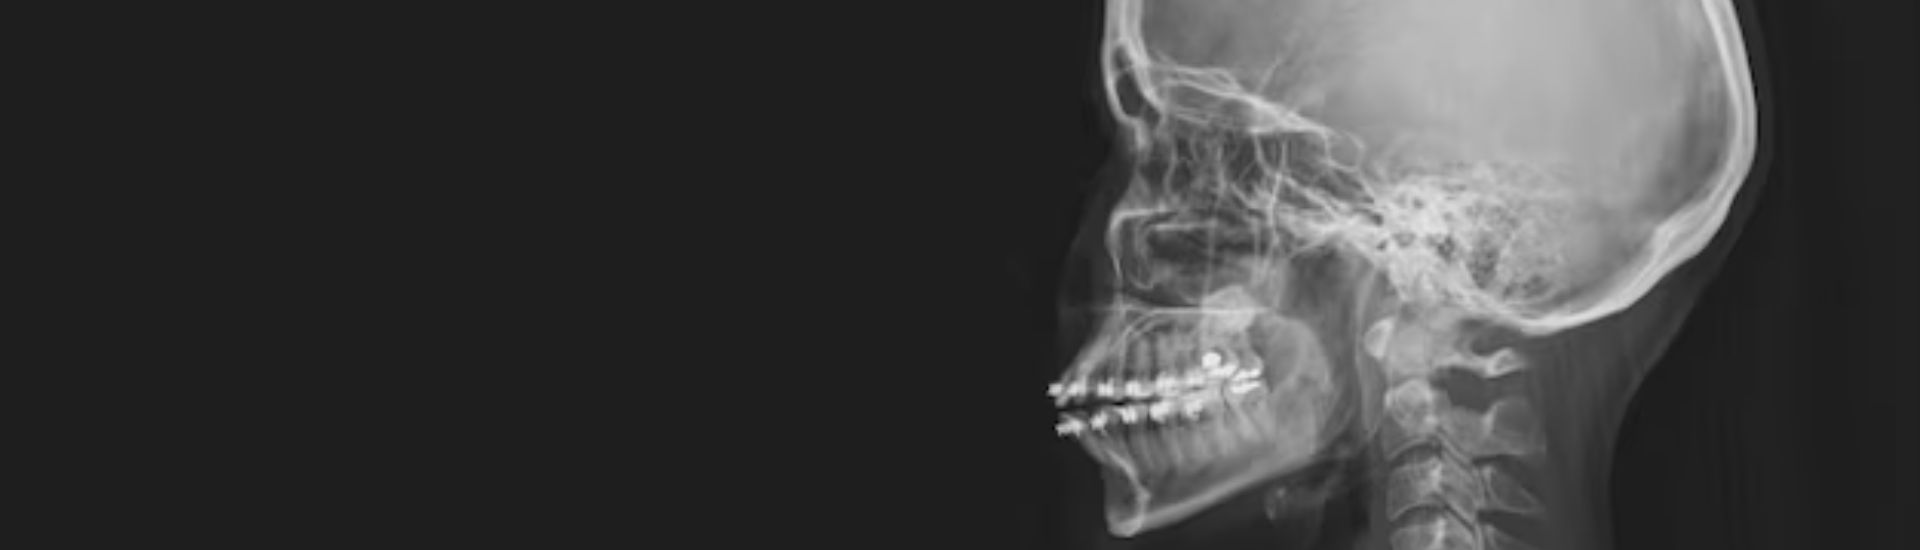

La RX Sella Turgica, o radiografia della sella turcica, è un esame diagnostico che permette di ottenere immagini dettagliate della sella turcica, una piccola depressione ossea situata alla base del cranio. Al suo interno si trova l’ipofisi, una ghiandola endocrina essenziale per la regolazione di numerosi processi fisiologici, come il metabolismo, la crescita e la funzione riproduttiva.

L’esame viene svolto in modo semplice e non invasivo presso il Poliambulatorio S-Medical Group di Sora. Il paziente viene fatto accomodare sul lettino radiografico e posizionato in maniera tale da consentire la visualizzazione ottimale della sella turcica. Attraverso l’utilizzo di raggi X, vengono catturate immagini da diverse angolazioni per garantire una valutazione completa della struttura ossea e dei tessuti circostanti. L’intero procedimento dura generalmente tra i 15 e i 30 minuti e non richiede anestesia.

La RX Sella Turgica consente di identificare numerose condizioni patologiche che interessano la sella turcica e l’ipofisi. Le immagini ottenute possono rivelare: